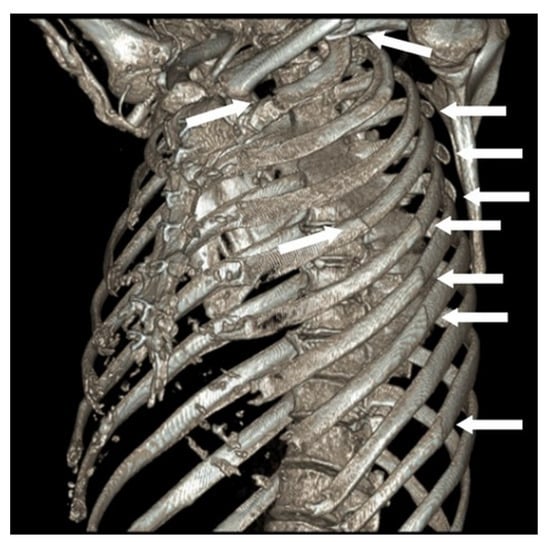

Figure 2. Preoperative 3-dimensional CT reconstruction of chest. Preoperative 3-dimensional CT reconstruction of chest—white arrows point to fracture sites.

After fixation, two 19 French intercostal catheters were inserted before closing. The thoracic wall muscles and subcutaneous fat were approximated with 2-0 Vicyrl and the skin was closed with subcuticular 3-0 Monocryl. The patient was monitored in the high dependence unit for 2 days with no complications. On day 7 of admission, the left clavicle was fixed with surgical plating. Functional lung expansion improved substantially (>50%) on day 8 of his admission, which corresponded to day 2 after SSRF. On day 10 of his admission, corresponding to day 4 after SSRF, he was able to perform incentive spirometry adequately (1200 mL). He was discharged on day 14 of his admission with no opioid analgesia and without supplemental oxygen. He was followed up in an outpatient clinic after 4 weeks, where his pain was demonstrably well controlled (0/10 at rest and 3/10 on exertion), and his chest X ray and chest CT revealed good expansion of his chests with plates and screws in situ (Figure 3B).